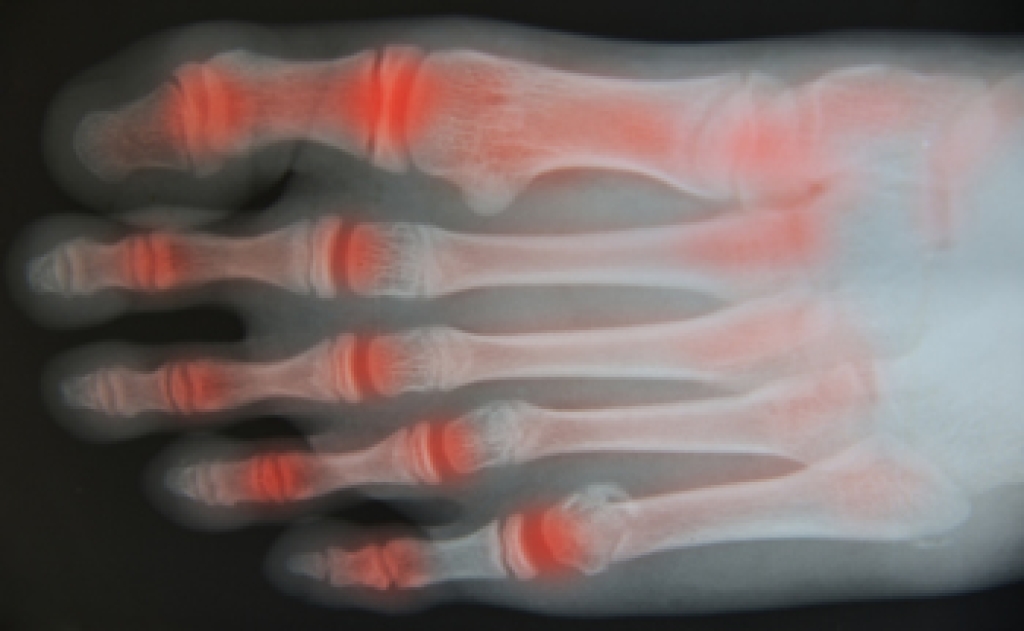

- Arthritis (such as Gout, Rheumatoid, and Osteoarthritis)

To figure out the cause of foot pain, podiatrists utilize several different methods. This can range from simple visual inspections and sensation tests to X-rays and MRI scans. Prior medical history, family medical history, and any recent physical traumatic events will all be taken into consideration for a proper diagnosis.